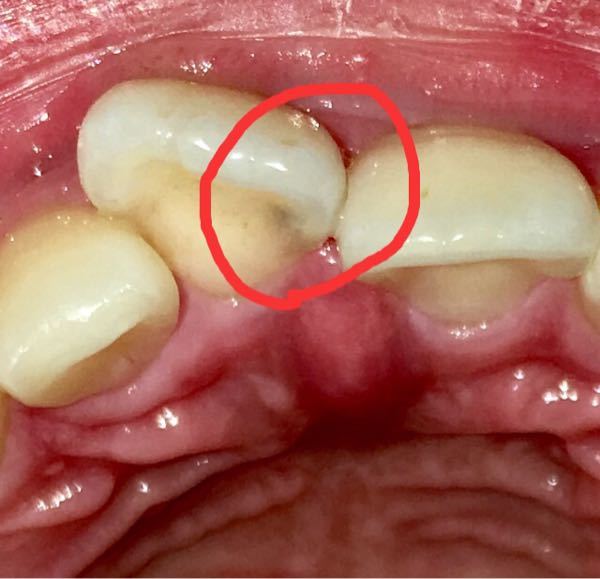

閲覧注意です。この前歯の虫歯はC2くらいですか?(画像あり

小児歯科 虫歯治療C2の症例(尾張旭市 7歳)-尾張旭市の歯科・歯医者

虫歯の治療③ 象牙質の虫歯【C2】 u2013 清瀬いんどう歯科|清瀬市松山の